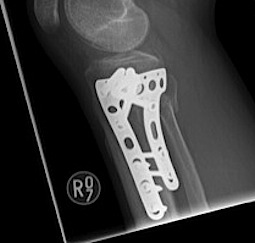

Type VI Bicondylar with Metaphyseal Fracture

Technique

- long locking plate minimally invasive with locking jig / MIPO

- proximal lag screws

- ensure correct alignment

- often use small medial buttress plate